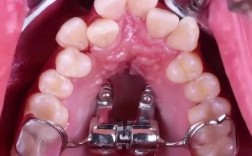

不同矫正方式带来的疼痛体验也有差异,传统金属托槽矫正初戴时,托槽可能刺激口腔黏膜,导致溃疡疼痛,加力时牙齿酸痛感较明显;隐形矫正器初戴时异物感较强,且可能因紧密贴合引起牙齿酸胀,但黏膜刺激较小,疼痛感更温和;自锁托槽因摩擦力小,加力时牙齿移动更轻柔,疼痛程度通常比传统托槽轻,是否拔牙也会影响疼痛感受,拔牙矫正需要移动更多牙齿,初期酸胀感可能更明显,但长期来看有利于牙齿排列稳定。